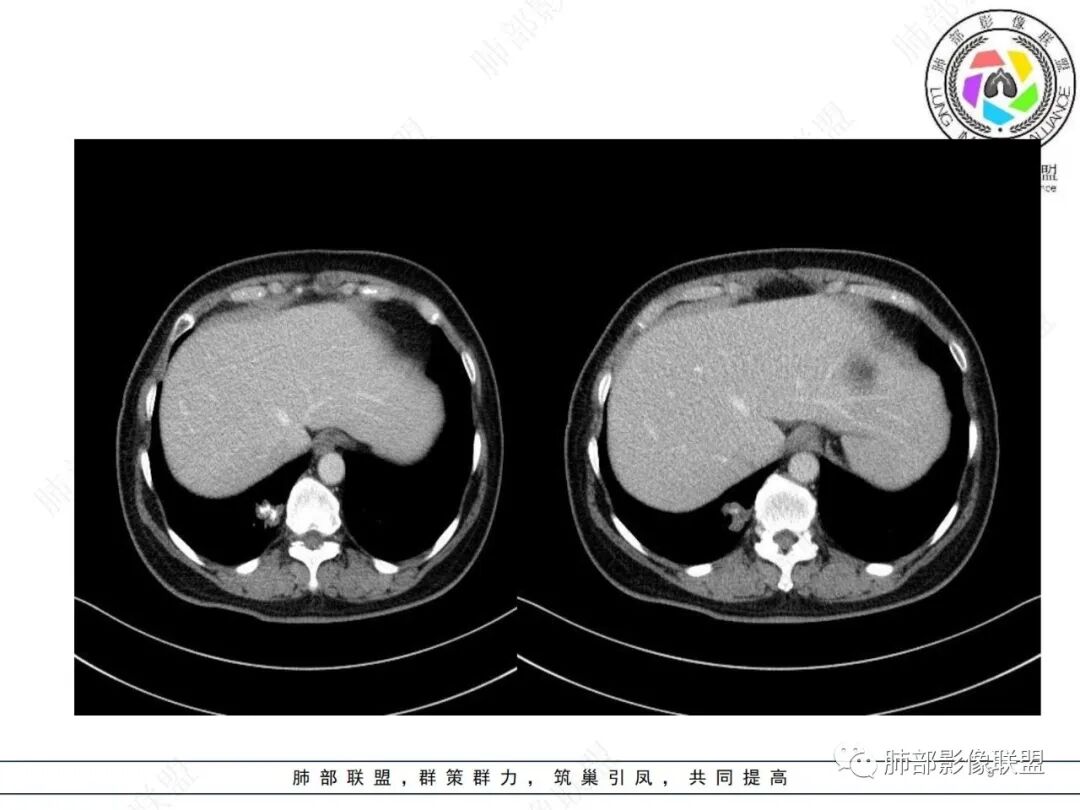

下肺胸膜下不规则结节影,边界较清楚,密度不均,中央见较大范围钙化区,未见明显胸膜牵拉,容易联想到钙化明显的病灶,多为良性,如软骨成分丰富的错构瘤,继发性肺结核的结核球等等……

1.本例病灶不够抱团,位于周边,钙化不具有爆米花“弧形”特征,也未见脂肪密度区,错构瘤的特征并不明显。

2.继发性肺结核的确值得怀疑,毕竟有结节堆砌感,钙化明显,不支持的地方在于病灶部分边缘存在较清楚的磨玻璃影,并且病灶的强化方式让人窦疑。

3.怀疑新生物有其合理性,磨玻璃密度区,强化方式等等。

病理“粘液腺癌”的报告可以“接受”,尽管本例影像学推断有一定难度。

4.关于病灶内钙化,尽管部分肺肿瘤可以出现钙化,但钙化如此密实,占比如此之大,究属少见,尚不能完全排除此前已经存在的可能。钙化灶的存在并不能豁免新生物的发生。

前后影像对比意义重大,既能够观测结节影是否进行性增大,还几乎可以证实钙化的来龙去脉!